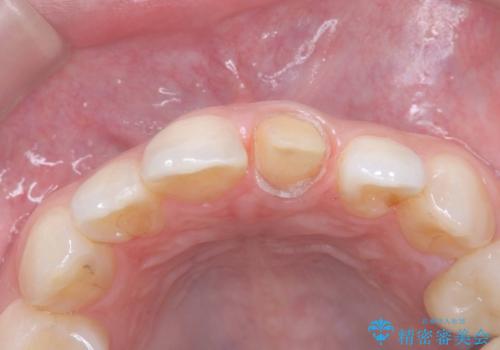

- 「前歯の色が気になる」を主訴に来院された患者様です。

前歯にプラスチックの材料が入っており、形と色が悪くなっていました。

失活歯だったため全体的に歯の色が暗くなっていました。

オールセラミッククラウンで治療を行い見た目の改善を行いました。